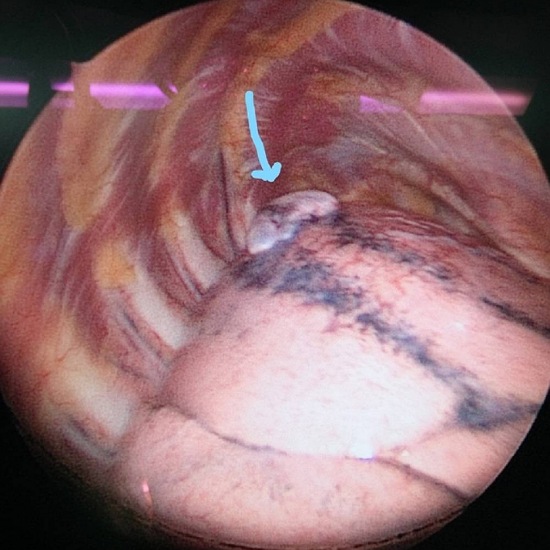

รศ.นพ.ศิระ เลาหทัย แพทย์ผู้เชี่ยวชาญศัลยศาสตร์ ทรวงอกเฉพาะทางด้านการผ่าตัดส่องกล้องในช่องทรวงอก โรงพยาบาลวชิรพยาบาล กล่าวว่าจากการวินิจฉัย ส่วนมากการทำ X-Ray หรือ ทำเอกซเรย์คอมพิวเตอร์ (CT Chest) หรือ MRI อาจพบได้ แต่อย่างไรก็ตามยังไม่มีการตรวจใดมีประสิทธิภาพที่สามารถวินิจฉัยโรคนี้ได้โดยตรง โดยในบางรายอาจพบถุงลมบริเวณยอดของปอดร่วมด้วยได้ (Lung Bleb) ในส่วนของการรักษาในโรคลมรั่วในเยื่อหุ้มปอดนี้ ประกอบด้วย 2 อย่าง ได้แก่1)การรักษาด้วยการผ่าตัด(ส่องกล้อง) และ2)การรักษาด้วยยา

โดยรักษาด้วยการผ่าตัดภาวะลมรั่วในเยื่อหุ้มปอดขณะมีประจำเดือนนั้น ในปัจจุบันภาวะลมรั่วในเยื่อหุ้มปอดสามารถทำได้โดยการผ่าตัดผ่านการส่องกล้อง (Video Assisted Thoracoscopic Surgery; VATS) หรือ การผ่าตัดเปิดแบบดั้งเดิม (Open Thoracotomy)โดยเป้าหมายของทั้ง 3 วิธี ได้แก่ 1. จัดการสาเหตุของลมรั่ว โดยการหาสาเหตุของลมรั่วจากปอดให้พบ เช่น ถุงลม (blebs, bullae) ที่แตกและทำการซ่อมแซมหรือตัดบริเวณส่วนนั้น 2. การทำสร้างพังผืด (Surgical Pleurodesis) ระหว่าง Parietal และ Visceral Pleura เพื่อทำให้เกิดการอักเสบ เพื่อลดอัตราการกลับมาเป็นซ้ำ โดยสามารถทำได้หลายวิธี เช่น การลอกเยื่อหุ้มปอด (Pleurectomy) หรือ การขูดบริเวณเยื่อหุ้มปอด (mechanical pleural abrasion ) และใส่สารเคมีบริเวณเยื่อหุ้มปอด (Chemical Pleurodesis) และ 3. ตัดบริเวณกระบังลมที่มีการกระจายตัวของช็อตโกแลตซีสต์ (Resection of Fenestrated Diaphragm) โดยผลของการผ่าตัดเปรียบเทียบระหว่างการผ่าตัดเปิดกับผ่าตัดส่องกล้องพบว่าผ่าตัดส่องกล้อง สามารถลดภาวะเสี่ยงได้ ดังนี้ 1. ลดภาวการณ์ปวดหลังจากการผ่าตัด 2. ลดระยะเวลาการนอนโรงพยาบาล และ3.ลดภาวะแทรกซ้อนของการผ่าตัด